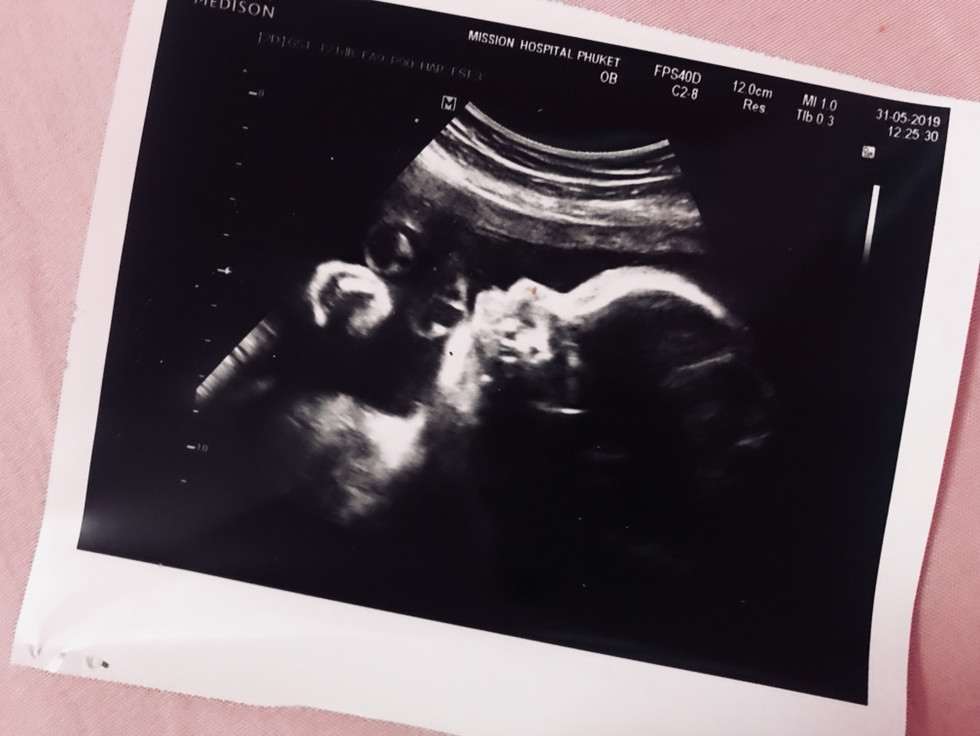

ลูกสาวจ้า